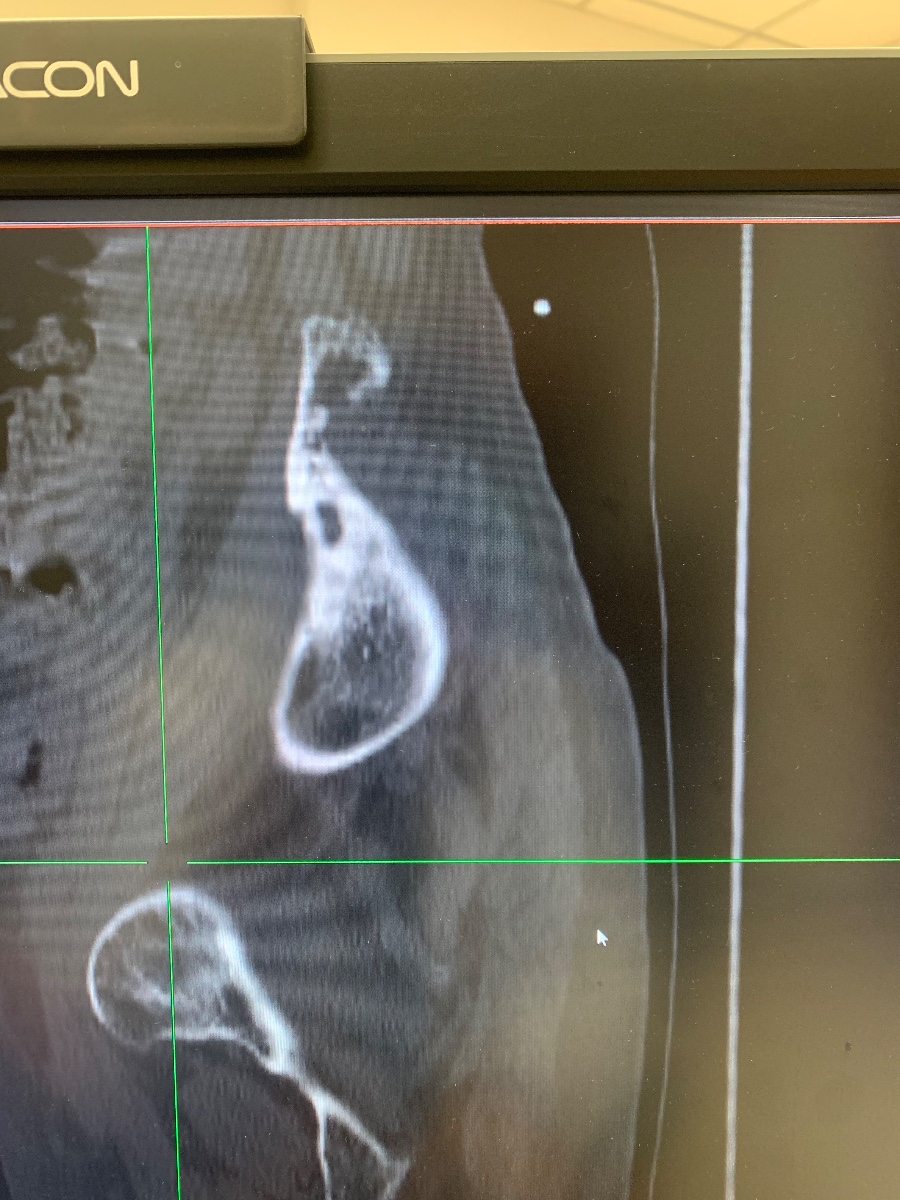

【病例讨论】左侧骶骨、髂骨病变

患者女,70岁,四年前因骶髂关节痛,于三级医院摄X片,提示骶髂关节炎,CT检查又考虑结核,但实验室等检查,未查到结核菌,但仍进行了抗结核治疗。未见旧片,今患者左侧乏力,左侧倾倒就诊。我院CT片如下图:

浆细胞瘤。

从部位来看,我觉得考虑骨巨细胞瘤,可以跨关节。鉴别脊索瘤和低度恶性软骨肉瘤。上面老师考虑浆细胞瘤,是不是有残存骨脊,有点像“微脑征”,但是我觉得浆细胞瘤是不是骨质破坏密度还要低一些?期待病理答案